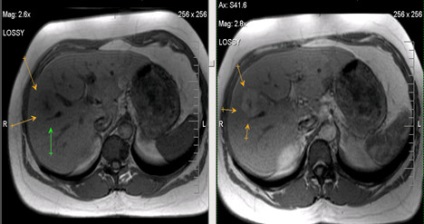

MRI képalkotó hepatocelluláris adenoma a máj

Hepatocelluláris rák (az US - hemangioma).

Hepatocelluláris rák (infiltratív formájában), a másodlagos lymphadenopathia.